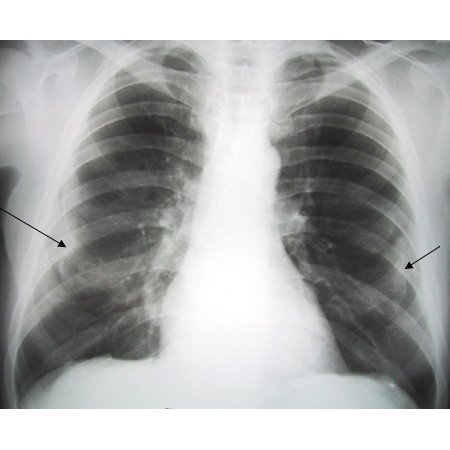

Posterior-anterior view of the chest with 'en face' pleural changes in the mid zones on the right and left (arrows)

From the personal collection of Kenneth D. Rosenman MD